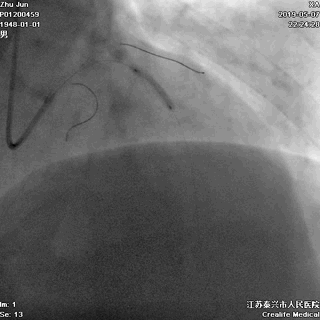

前降支植入第一枚STENT

前降支-左主干STENT定位和植入

五、高压后扩张

---保证STENT充分贴壁

非顺应性球囊高压后扩,保证STENT充分贴壁

六、主干支架近段优化

---不能省略的步骤

大一号球囊高压扩张近段STENT

七、最终结果

---即刻效果完美

手术即刻效果完美,患者存活